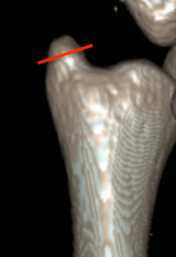

Classification ulna styloid fractures

| Type 1: Tip | Type 2: Base | Type 3: Proximal to styloid |